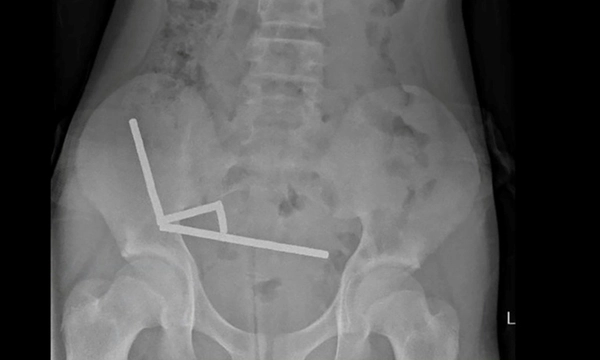

Phim chụp X-quang cho thấy một cảnh tượng đáng sợ: các viên nam châm đã dính lại với nhau thành bốn đường thẳng bên trong ruột của cậu bé.

Lực hút cực mạnh của nam châm đã gây ra tình trạng hoại tử (chết mô) nghiêm trọng tại bốn vùng trong ruột non và manh tràng (một phần của ruột già) của cậu bé.